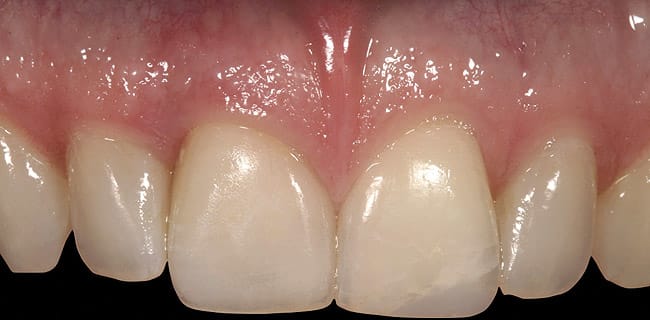

This patient presented with a non-restorable left central incisor due to external root resorption, as shown in the pre-treatment radiograph (Figure 1) and clinical photograph (Figure 2). The patient had good bone levels. The papilla positions were also good, but the cervical margins had some asymmetry with recession on the adjacent teeth. The goal was to preserve the papilla levels and the facial gingival margin level on the central incisors while also improving the gingival levels on the lateral incisors. Due to the patient’s cost concerns, the lateral incisors were not treated except for extending the CTG on the left central incisor only. A custom healing abutment was used to support the peri-cervical soft-tissue form.

The adjacent central incisor crown was to be replaced, which made it logical to do a cantilever provisional restoration as an interim provisional for the implant. The tooth was extracted in a flapless protocol. The implant was placed; in addition, a CTG was performed using a tunnel approach. Two weeks later, the soft-tissue volume was thick and well preserved. The final lithium-disilicate restorations were cut back and layered; they were opaque enough to mask the darkness of the endodontically treated right central incisor. The CTG resulted in preserving the cervical soft-tissue root prominence and also corrected the recession on the left lateral incisor. The all-ceramic restorations and zirconium abutments made the implant indistinguishable from the adjacent natural tooth (Figure 3).